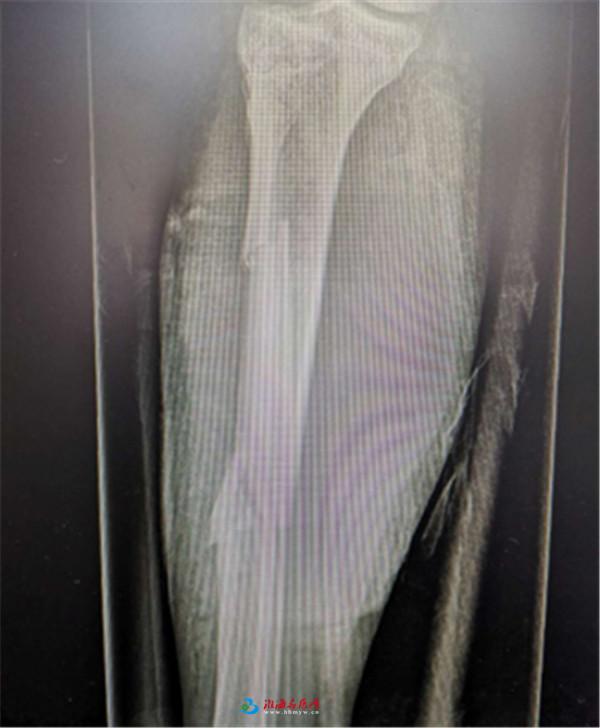

术后X线片

在对患者的头颅、胸部、腹部CT检查后,确认患者未见明显手术禁忌症的情况下,在沈金虎主任带领下,历经2个多小时给患者成功固定骨折,彻底清创伤口,至凌晨5点40左右手术结束。手术进行得很顺利,术中麻醉师给予患者及时进行了输血、补液等抗休克对症支持治疗。